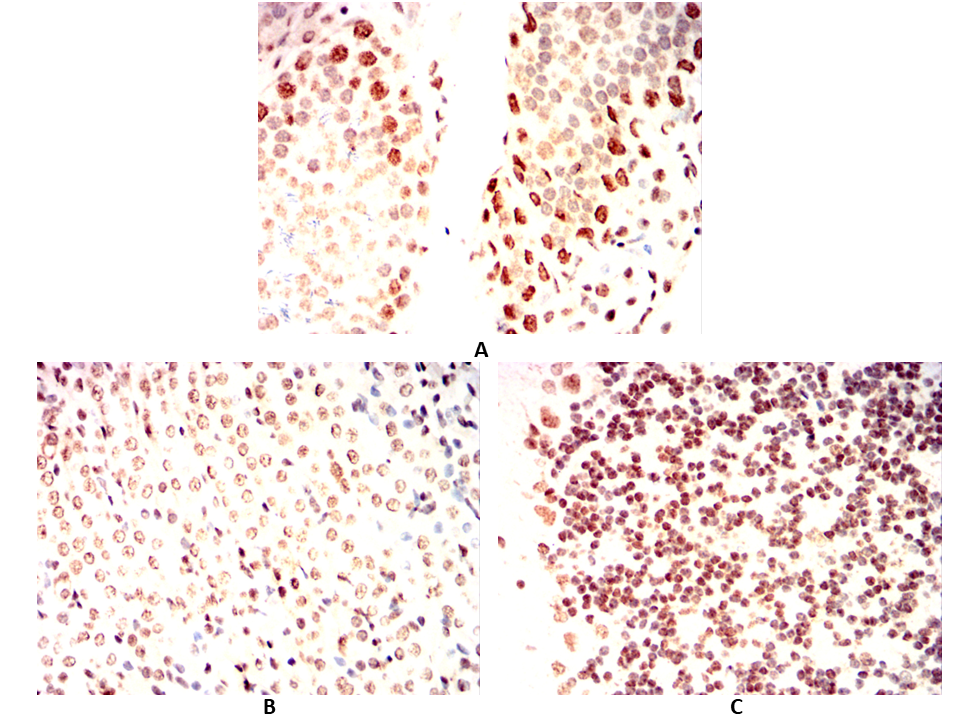

Immunohistochemical analysis of paraffin-embedded Rat testicles(A)Rat kidney(B)Rat cerebellum(C) using ESR1 mouse mAb with DAB staining.